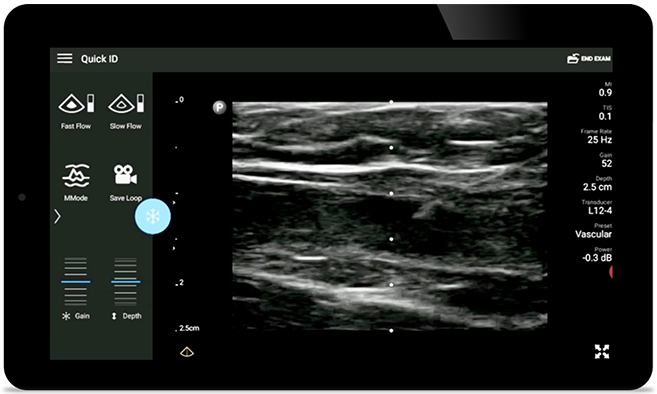

Decrease complications of CVC insertions

Real-time ultrasound guidance can improve the accuracy and safety of CVC insertions.

• 12 to 4 MHz extended operating frequency range • Aperture size: 34mm • 2D, steerable color Doppler, M-mode, advanced XRES and multivariate harmonic imaging, SonoCT • High resolution imaging for shallow applications: soft tissue, vascular, superficial, musculoskeletal, and lung • Center line marker • USB-C transducer with replaceable cable